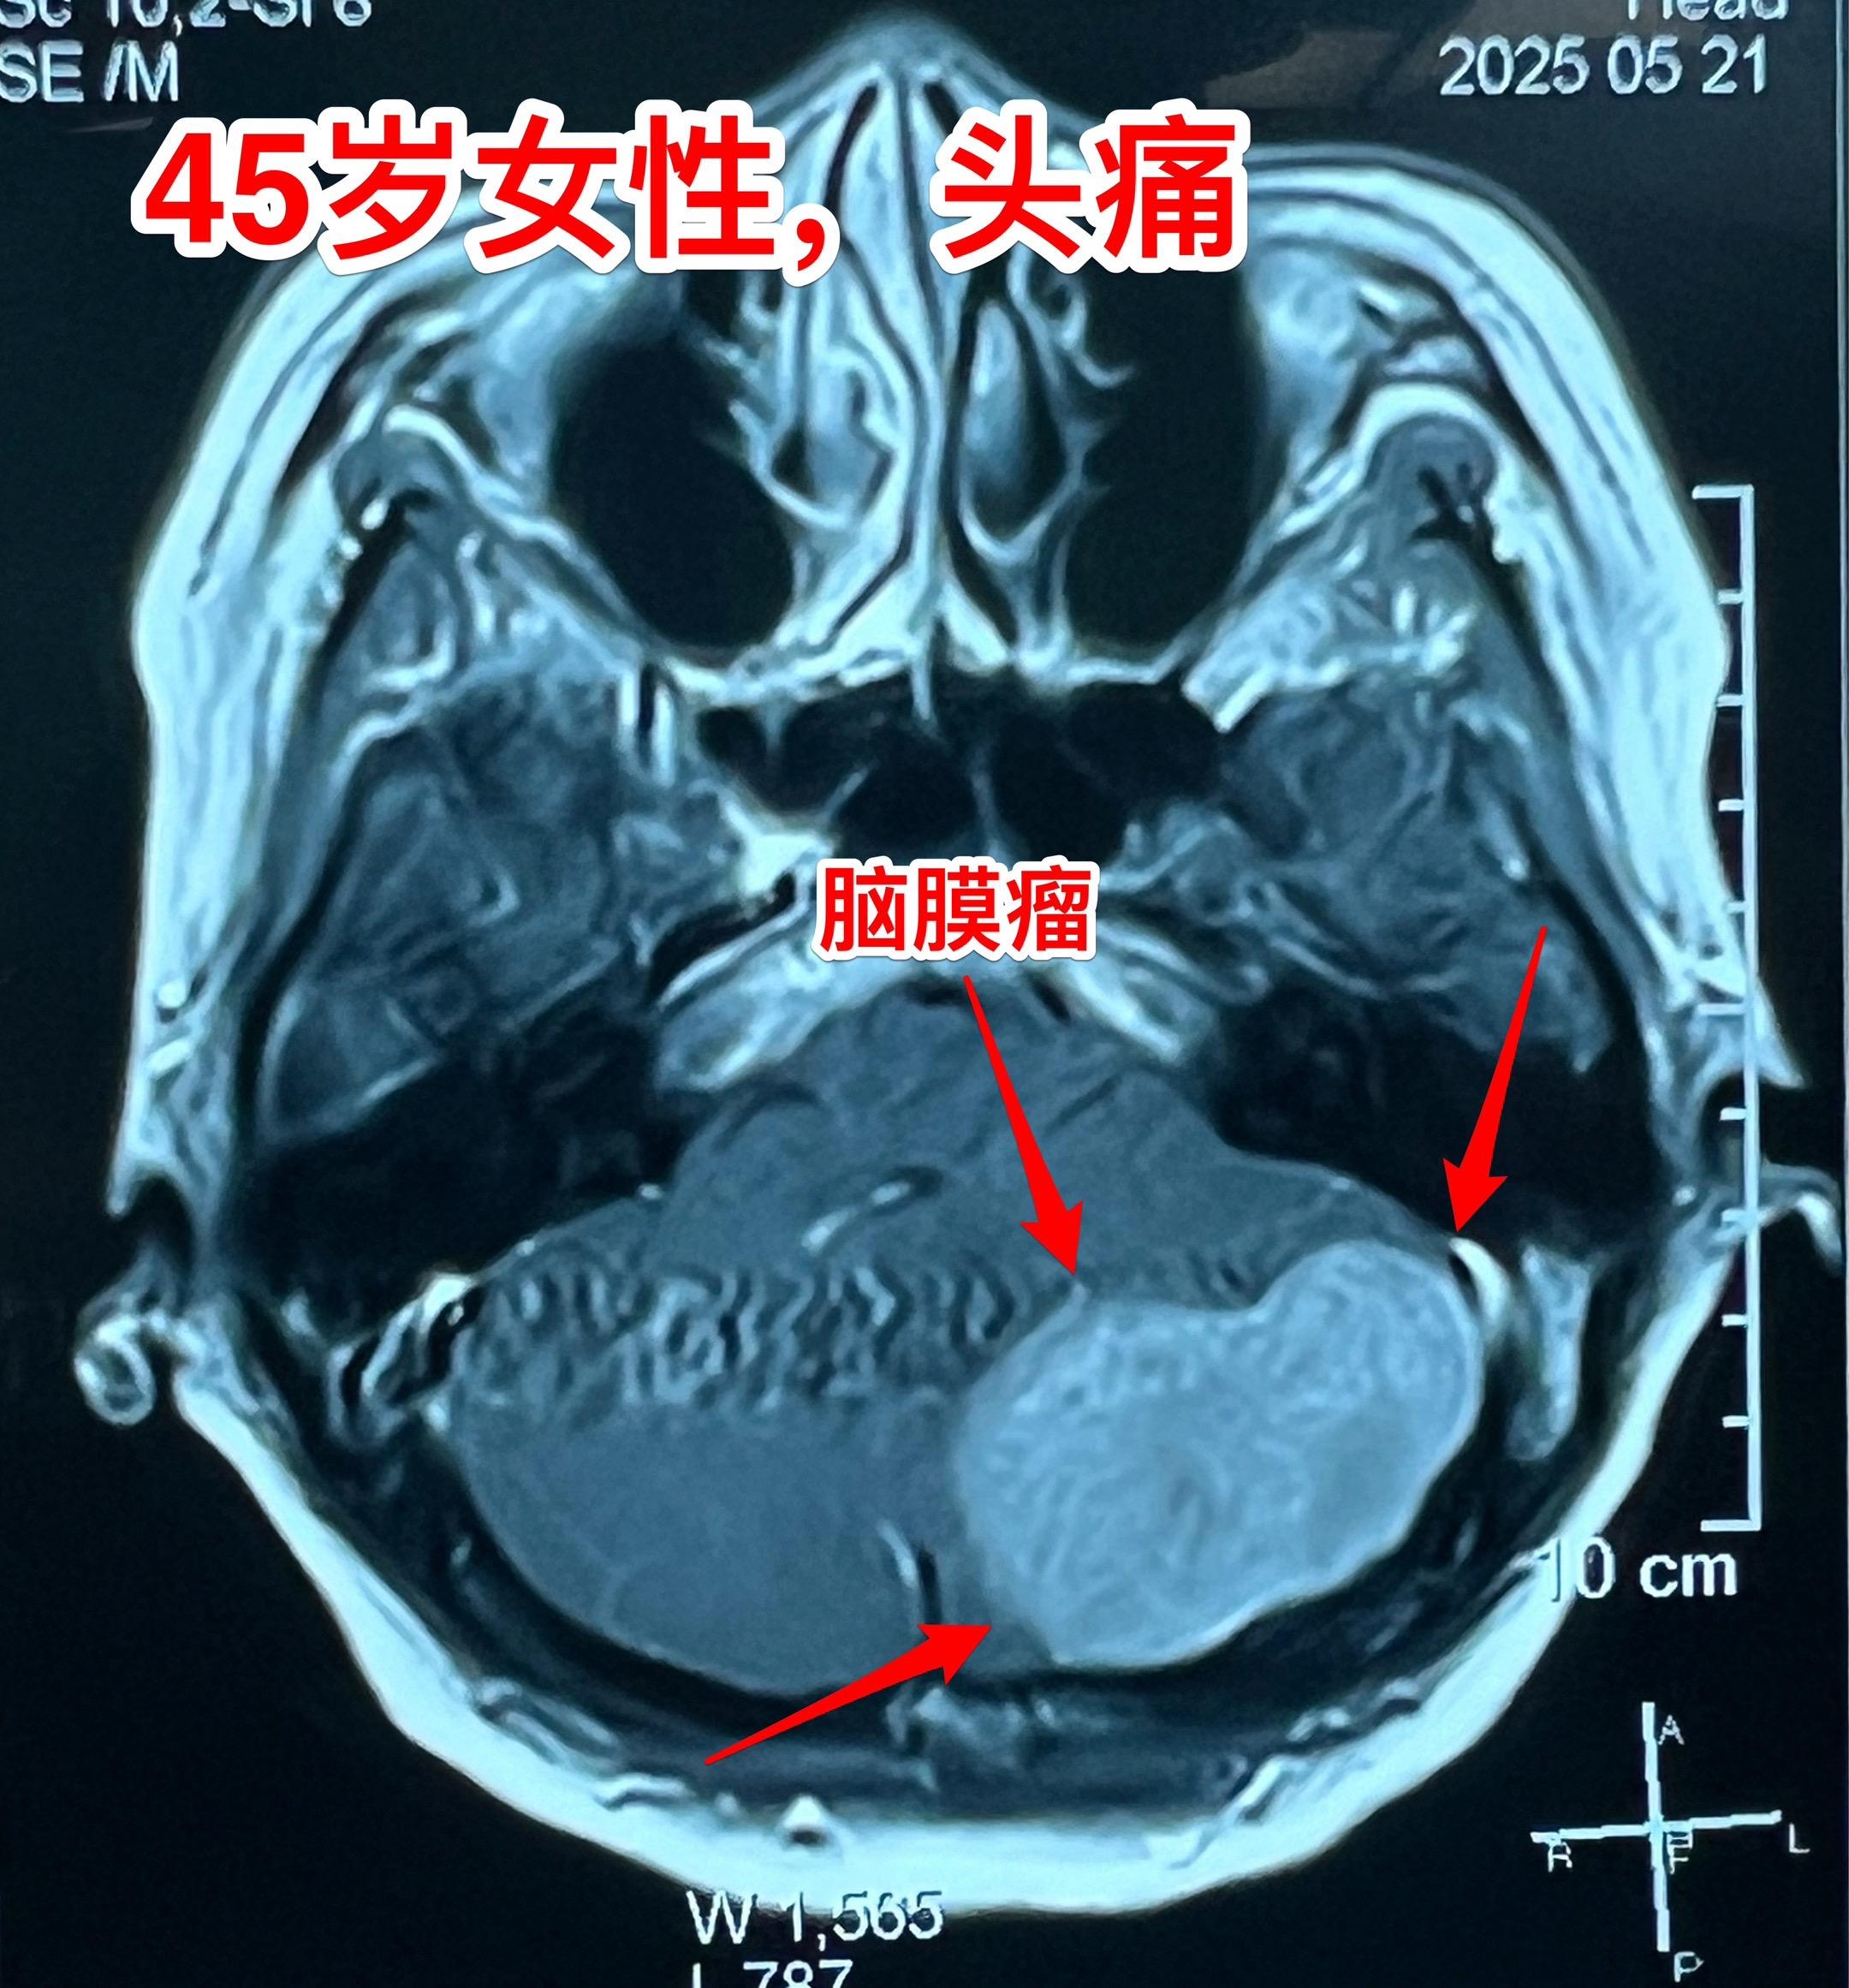

45岁女性因头痛发现脑膜瘤。45岁呼伦贝尔女性,在北京工作。头痛症状不剧烈,无呕吐。到医院就医,作头部CT检查发现可疑问题,再作磁共振检查发现左侧小脑表面有个巨大的脑膜瘤,伴有脑积水。 5月23日作了手术(只能是开颅手术)将脑膜瘤完全切除。 这样的脑膜瘤属于相对浅表位置的肿瘤,比颅咽管瘤手术要容易的多。脑膜瘤虽然是良性肿瘤,也有一定的复发率。